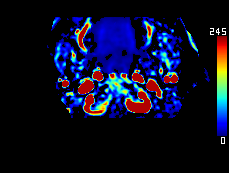

DeepClue-Precise CT 측부혈류영상

Perfusion CT를 이용한 측부혈류영상

동맥기

모세혈관기

조기정맥기

후기정맥기

지연기